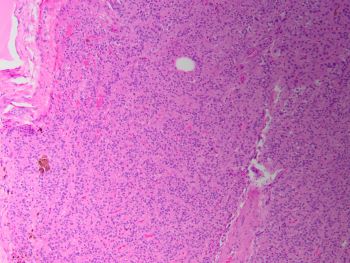

A middle-aged male presents with a solitary thyroid mass. Fine-needle aspiration and lobectomy are performed and representative sections are shown.

The cytology smears show follicular cell groups with scant colloid and intermixed cells with large hyperchromatic nuclei and abundant cytoplasm. Histologic sections show an encapsulated lesion with follicular architecture. Scattered cells enlarged cells with bizarre nuclei are also noted, but this is more consistent with benign atypia seen in endocrine organs.